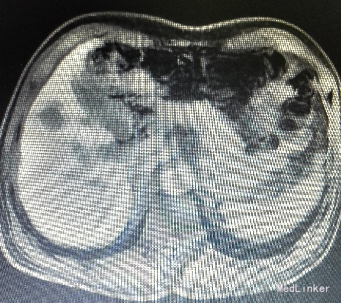

入院后行腹部CT检查,提示肝S5病灶,考虑小肝癌可能性大。